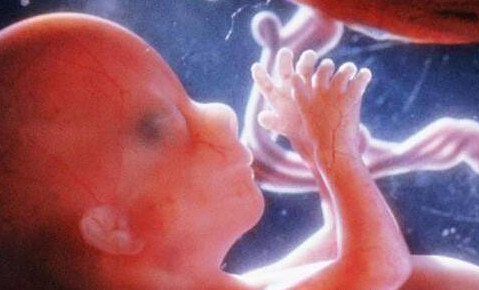

是指怀孕时子宫羊膜腔内的液体。在整个怀孕过程中,它是维持胎儿生命所不可缺少的重要成分。在胎儿的不同发育阶段,羊水的来源也各不相同。在妊娠第一个三月期,羊水主要来自胚胎的血浆成分;之后,随着胚胎的器官开始成熟发育,其他诸如胎儿的尿液、呼吸系统、胃肠道、脐带、胎盘表面等等,也都成为了羊水的来源。

● 在妊娠期,羊水能缓和腹部外来压力或冲击,使胎儿不至直接受到损伤。

● 羊水能稳定子宫内温度,使不至有剧烈变化,在胎儿的生长发育过程中,胎儿能有一个活动的空间,因而,胎儿的肢体发育不至形成异常或畸形。

● 羊水可以减少妈妈对胎儿在子宫内活动时引起的感觉或不适。